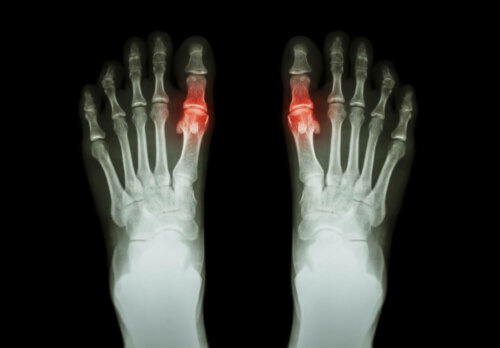

Cette pathologie a tendance à se manifester par des douleurs et des difficultés à bouger l’articulation affectée. Parfois, cela s’accompagne de raideur dans cette même zone ainsi qu’un gonflement. L’arthrite peut toucher une seule articulation ou plusieurs en même temps. Elle peut même être symétrique ou non.

Chaque type a ses particularités. Et la durée des symptômes est généralement variables. Par exemple, l’arthrite rhumatoïde est une arthrite symétrique qui affecte les petites articulations comme celles des doigts de la main. De son côté, la goutte apparaît souvent sous la forme d’arthrite dans une seule articulation.